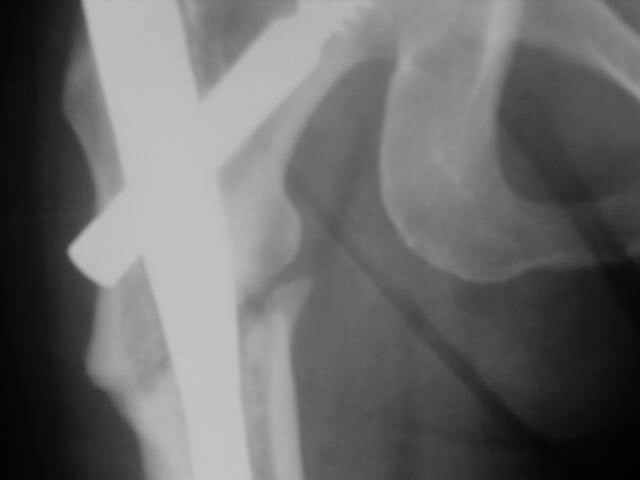

Advice on this case would be appreciated. 59 year old female normal body weight and nonsmoker.

Now 11 months out from initial fixation. No clinical evidence of infection. Closed fracture initially. CT confirms minimal bridging bone. Weightbearing pain in proximal thigh. My initial thought was onlay autogenous bone graft with BMP supplementation and leaving fixation as is. Any benefit to revision fixation and if so what implant? Her ROM and length are symmetric. Thanks.

I'd get a true AP of the hip view & compare to same of normal side: I bet you will find enough varus present (combined with mild extension seen on lateral) to site malalignment as cause and consider axis correction as the solution to nonunion.

I would like to see an ap of both hips, it looks like there is a significant amount of varus that should be corrected.